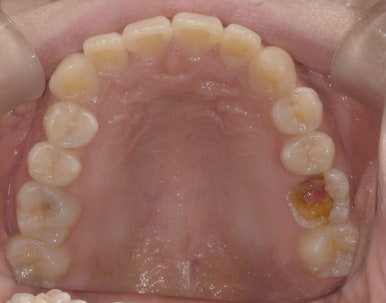

임플란트 수술 전 구내사진과 수술 후 엑스레이 사진

30대 여성

(전) 2023-04-20 (후) 2023-07-03

두번째 환자분은 30대 초반의 여성분입니다. 충치검진을 위해 치과에 오신 분인데요.

수술 전 치아 상태를 먼저 보시면 왼쪽(사진상 오른쪽) 위 어금니가 많이 썩어있죠?

우식이 깊은 상태라 발치 후 임플란트를 제안해드렸고 다행히 이 환자분도 발치 당일 임플란트 식립이 가능해 바로 수술을 진행했습니다.

수술 2개월 후 잇몸뼈와 임플란트 픽스처가 잘 유착된 것으로 확인해 7월 초에 보철물까지 올려 마무리했습니다.